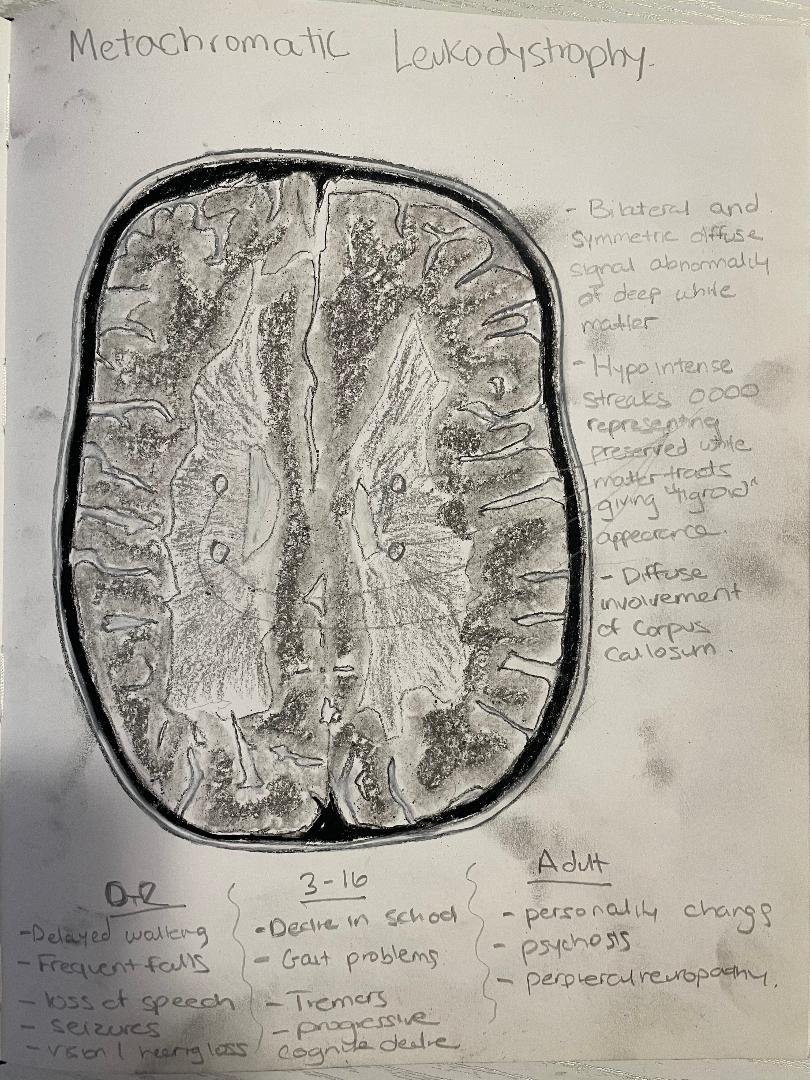

Metachromatic leukodystrophy